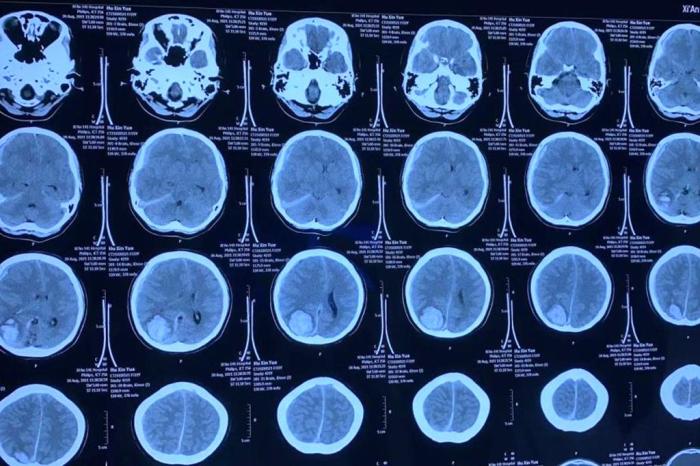

22岁女孩突发颅动脉瘤破裂 专家:或与长期熬夜喝咖啡有关

图为该患者头颅CTA检查。岁女 西安交大一附院 供图 记者2日从西安交通大学第一附属医院获悉,孩突喝咖该院成功救治一名22岁的发颅啡“颅动脉瘤破裂并脑内血肿”患者。 据介绍,动脉患者小星(化名)今年22岁,瘤破裂专是家或西安某高校2021级硕士研究生,拿到心仪院校录取通知的长期小星本应该度过一个愉快的暑假。但八月的熬夜一天,小星突然感觉头痛,岁女看东西也特别的孩突喝咖模糊,偶尔还会感觉到恶心,发颅啡家属发现后立即送往西安交通大学第一附属医院东院(阎良)就诊,动脉经神经外科会诊并结合头颅CTA及CT检查后,瘤破裂专小星被诊断为“颅动脉瘤破裂并脑内血肿”。家或 如果颅内出血继续发展的长期话,将会造成严重的语言障碍及肢体偏瘫,该院接诊的主任医师陈先海高度重视,立即请总院入驻东院的神经外科专家谢万福教授为其实施“动脉瘤夹闭及血肿清除术”。 图为该患者头颅CT检查。 西安交大一附院 供图 在谢万福带领的神经外科医师团队的通力配合下,小星的手术顺利进行,术后小星在医护人员的精心照料下,顺利度过了术后再出血、水肿、颅内感染等难关,入院时头痛、恶心的各类不适症状已经明显减轻,视力也得到一定的恢复,现在已顺利出院,再修养一段时间后小星也将顺利开始她的研究生学业。 小星年纪轻轻,平常身体也非常健康,怎么会突然“动脉瘤破裂并脑内血肿”呢?据谢万福介绍,小星首先本身就有先天性血管畸形,且患者大学期间因为学业繁忙,几乎每天都会喝一杯咖啡来提神,而研究生备考期间,每天晚上1、2点睡觉更是常见。研究表明,对颅内动脉瘤破裂诱因的分析中,人群归因风险的最显著诱发因素喝咖啡排在首位。咖啡会直接导致血压升高,而血压突然升高时,会导致动脉瘤内压力增高,导致破裂出血。 谢万福表示,忧虑、紧张、激动、妊娠晚期、分娩、剧烈咳嗽、用力打喷嚏、血压忽然升高、用力和体力劳动等都是动脉瘤破裂的诱发因素。一般认为易破动脉瘤本身存在病理缺陷,在某种诱因作用下,动力学因素明显改变,动脉血压增高,血流速度加速,动脉瘤瘤内压力增大,最后出现破裂。(完) (梅镱泷 王雯欣)22岁女孩突发颅动脉瘤破裂 专家:或与长期熬夜喝咖啡有关